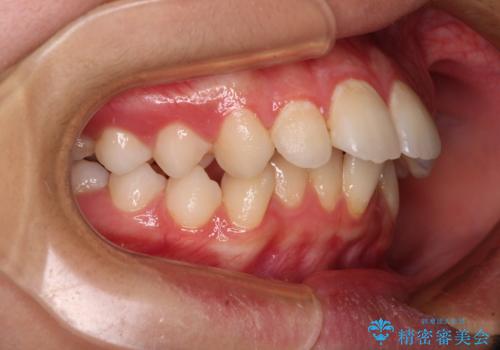

- 上顎前歯の突出感を気にして来院された患者様です。

舌の突出癖などにより、上下前歯の間に指が入るくらい隙間のできる状態でした。

下顎は叢生があったため、上下左右の第一小臼歯4本を抜歯し、更には口元の突出感を大きく改善させるために、上顎臼歯を後方に移動させるための補助装置をしようし、ワイヤー装置にて矯正治療を行うこととしました。